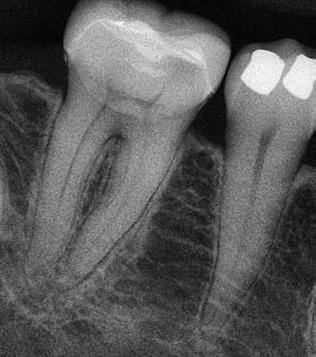

Krell és Caplan kutatásában 2086 repedt fogat vizsgáltak meg. A vizsgált fogak között leggyakrabban a második alsó nagyőrlőfogak (36%), majd ezt követően az első alsó nagyőrlők (27%), és végül az első felső nagyőrlők (18%) fordultak elő. A kutatási eredményeik szerint a fogbél állapota nem befolyásolta jelentős mértékben a kezelés várható kimenetelét. (Irreverzibilis pulpitis 85%; necrosis 80%; korábban gyökérkezelt 74%). A kimenetel szempontjából ugyanígy indifferens volt a páciensek neme, életkora, a kezelés időpontja, a fog pozíciója, a fog helyreállítása során használt anyag típusa, valamint az érintett fogfelszínek száma. 2014 júliusában egy 45 éves hölgy páciens azzal a panasszal kereste fel a rendelőnket, hogy nagyjából 10 napja egy fájdalmas duzzanat alakult ki a jobb felső első kisőrlője koronája mellett (14). A klinikai vizsgálat során egy amalgámtömést találtunk a panaszos fogban. A tömés széli zárása nem volt megfelelő, a disztális záróléc és a tömés között rést tapasztaltunk. A fog disztobukkális és linguális felszíne mellett 8 mm-es csontos tasakokat mértünk. A periapikális felvételen az 14-es foggyökér disztális felszínének megfelelően vertikális irányú radiolucens felritkulást észleltünk. A klinikai vizsgálat során a mesiális zárólécet kettéválasztó törésvonalat detektáltunk (17–18. ábra). A fogszenzibilitás vizsgálata során negatív eredményt kaptunk. A páciensnek ismertettük az elérhető terápiás lehetőségeket: 1, a 14-es fog eltávolítása, majd a foghiány 3 tagú cementezett híddal történő pótlása; 2, a 14-es fog eltávolítása, kemény- és lágyszöveti augmentáció, majd implantátum behelyezése; 3, a 14-es fog gyökérkezelése, gyökértömése és ezt követően a csücsökborítást biztosító restaurátum készítése. Arra is felhívtuk a páciens figyelmét, hogy a 3. terápiás lehetőség választása esetén nem tudjuk a fogmegtartás sikerességét garantálni, de végül – főként anyagi okok miatt – mégis ezt a terápiás opciót választotta. Fontos megjegyezni, hogy a repedt fogak ellátási lehetőségeit a törésvonal mélysége, elhelyezkedése, lefutása nagyban befolyásolja. A kezelés megtervezése során a fog és a fogat körülvevő szövetek állapotával kapcsolatos számtalan különböző faktort kell egyidejűleg figyelembe vennünk. A gyökérkezelést követően a gyökértömést meleg vertikális kondenzációs technikai alkalmazásával készítettük el (19. ábra). A hozzáférési nyílást folyékony és hibrid kompozit tömőanyag segítségével zártuk. A zárás elkészítése során a dr. David Clark által kifejlesztett Bioclear matricarendszert alkalmaztuk. A 6 éves kontroll során készített (2020) röntgenfelvételen a csontos defektus telődése volt megfigyelhető. Ez is a parodontális defektus gyógyulását igazolta (20–21. ábra).

17. ábra: A 14-es fog gyökerének disztális felszíne mellett vertikális csontpusztulásra utaló jelek észlelhetőek. Klinikailag ezen a területen 8 mm mélységű tasakmélységet mértünk. – 18. ábra: A 14-es fog disztális zárólécének megfelelően törésvonal észlelhető, ugyanakkor a csücskök teljes szeparálódására utaló jelek nem láthatóak. Az amalgámtömés eltávolítását követően jól megfigyelhető volt a törésvonal teljes lefutása. – 19. ábra: A gyökértömés elkészítése során meleg vertikális kondenzációs technikát alkalmaztunk. A felvételeken oldalcsatornák jelenlétére utaló jelek is észlelhetőek. – 20–21. ábra: A 2020-ban készült kontrollfelvételeken jól látható a csontos defektus telődése. A radiológiai jelek alapján (jól lekövethető gyökérhártyarés) a parodontális ligamentumok regenerációját is vélelmezzük.